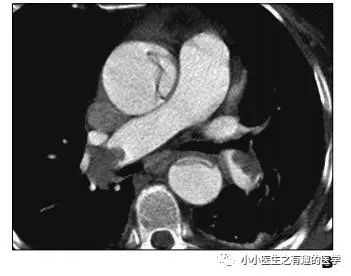

不光是肺栓塞,连主动脉夹层,都发现了。

牛。我来标记一下。